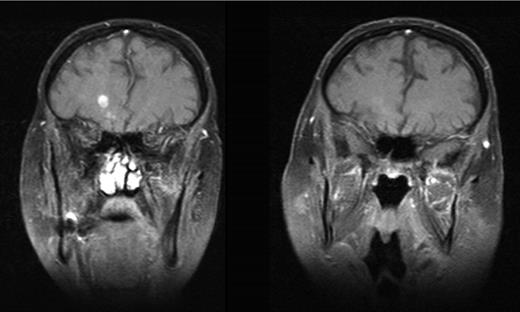

MRI scans before and during continuous dasatinib therapy. The left picture shows a representative MRI slice before dasatinib treatment. The right slide shows the same area approximately 9 months later. Pictures are representative of a total of 4 lesions with similar development.

Initial treatment included 5 courses of intravenous methotrexate (4 g/m2/day over days 1-2) and ifosfamide (1.5 g/m2/day over days 3-5), which led to rapid improvement of neurologic symptoms. At relapse, salvage chemotherapy included intravenous cytarabine (3 g/m2 twice per day over days 1-2), mitoxantrone (10 mg/m2/day over days 2-3), and intrathecal methotrexate (15 mg/day on day 1). Although initially successful, the patient later relapsed with an increase in the size and number of the cerebral lesions. Oral dasatinib (70 mg twice per day) was started and led to a complete regression of lesions visible on MRI and neurologic disease. The patient is currently in remission (> 12 months) with no measurable monoclonal lymphocyte population in blood and bone marrow on continuous therapy.